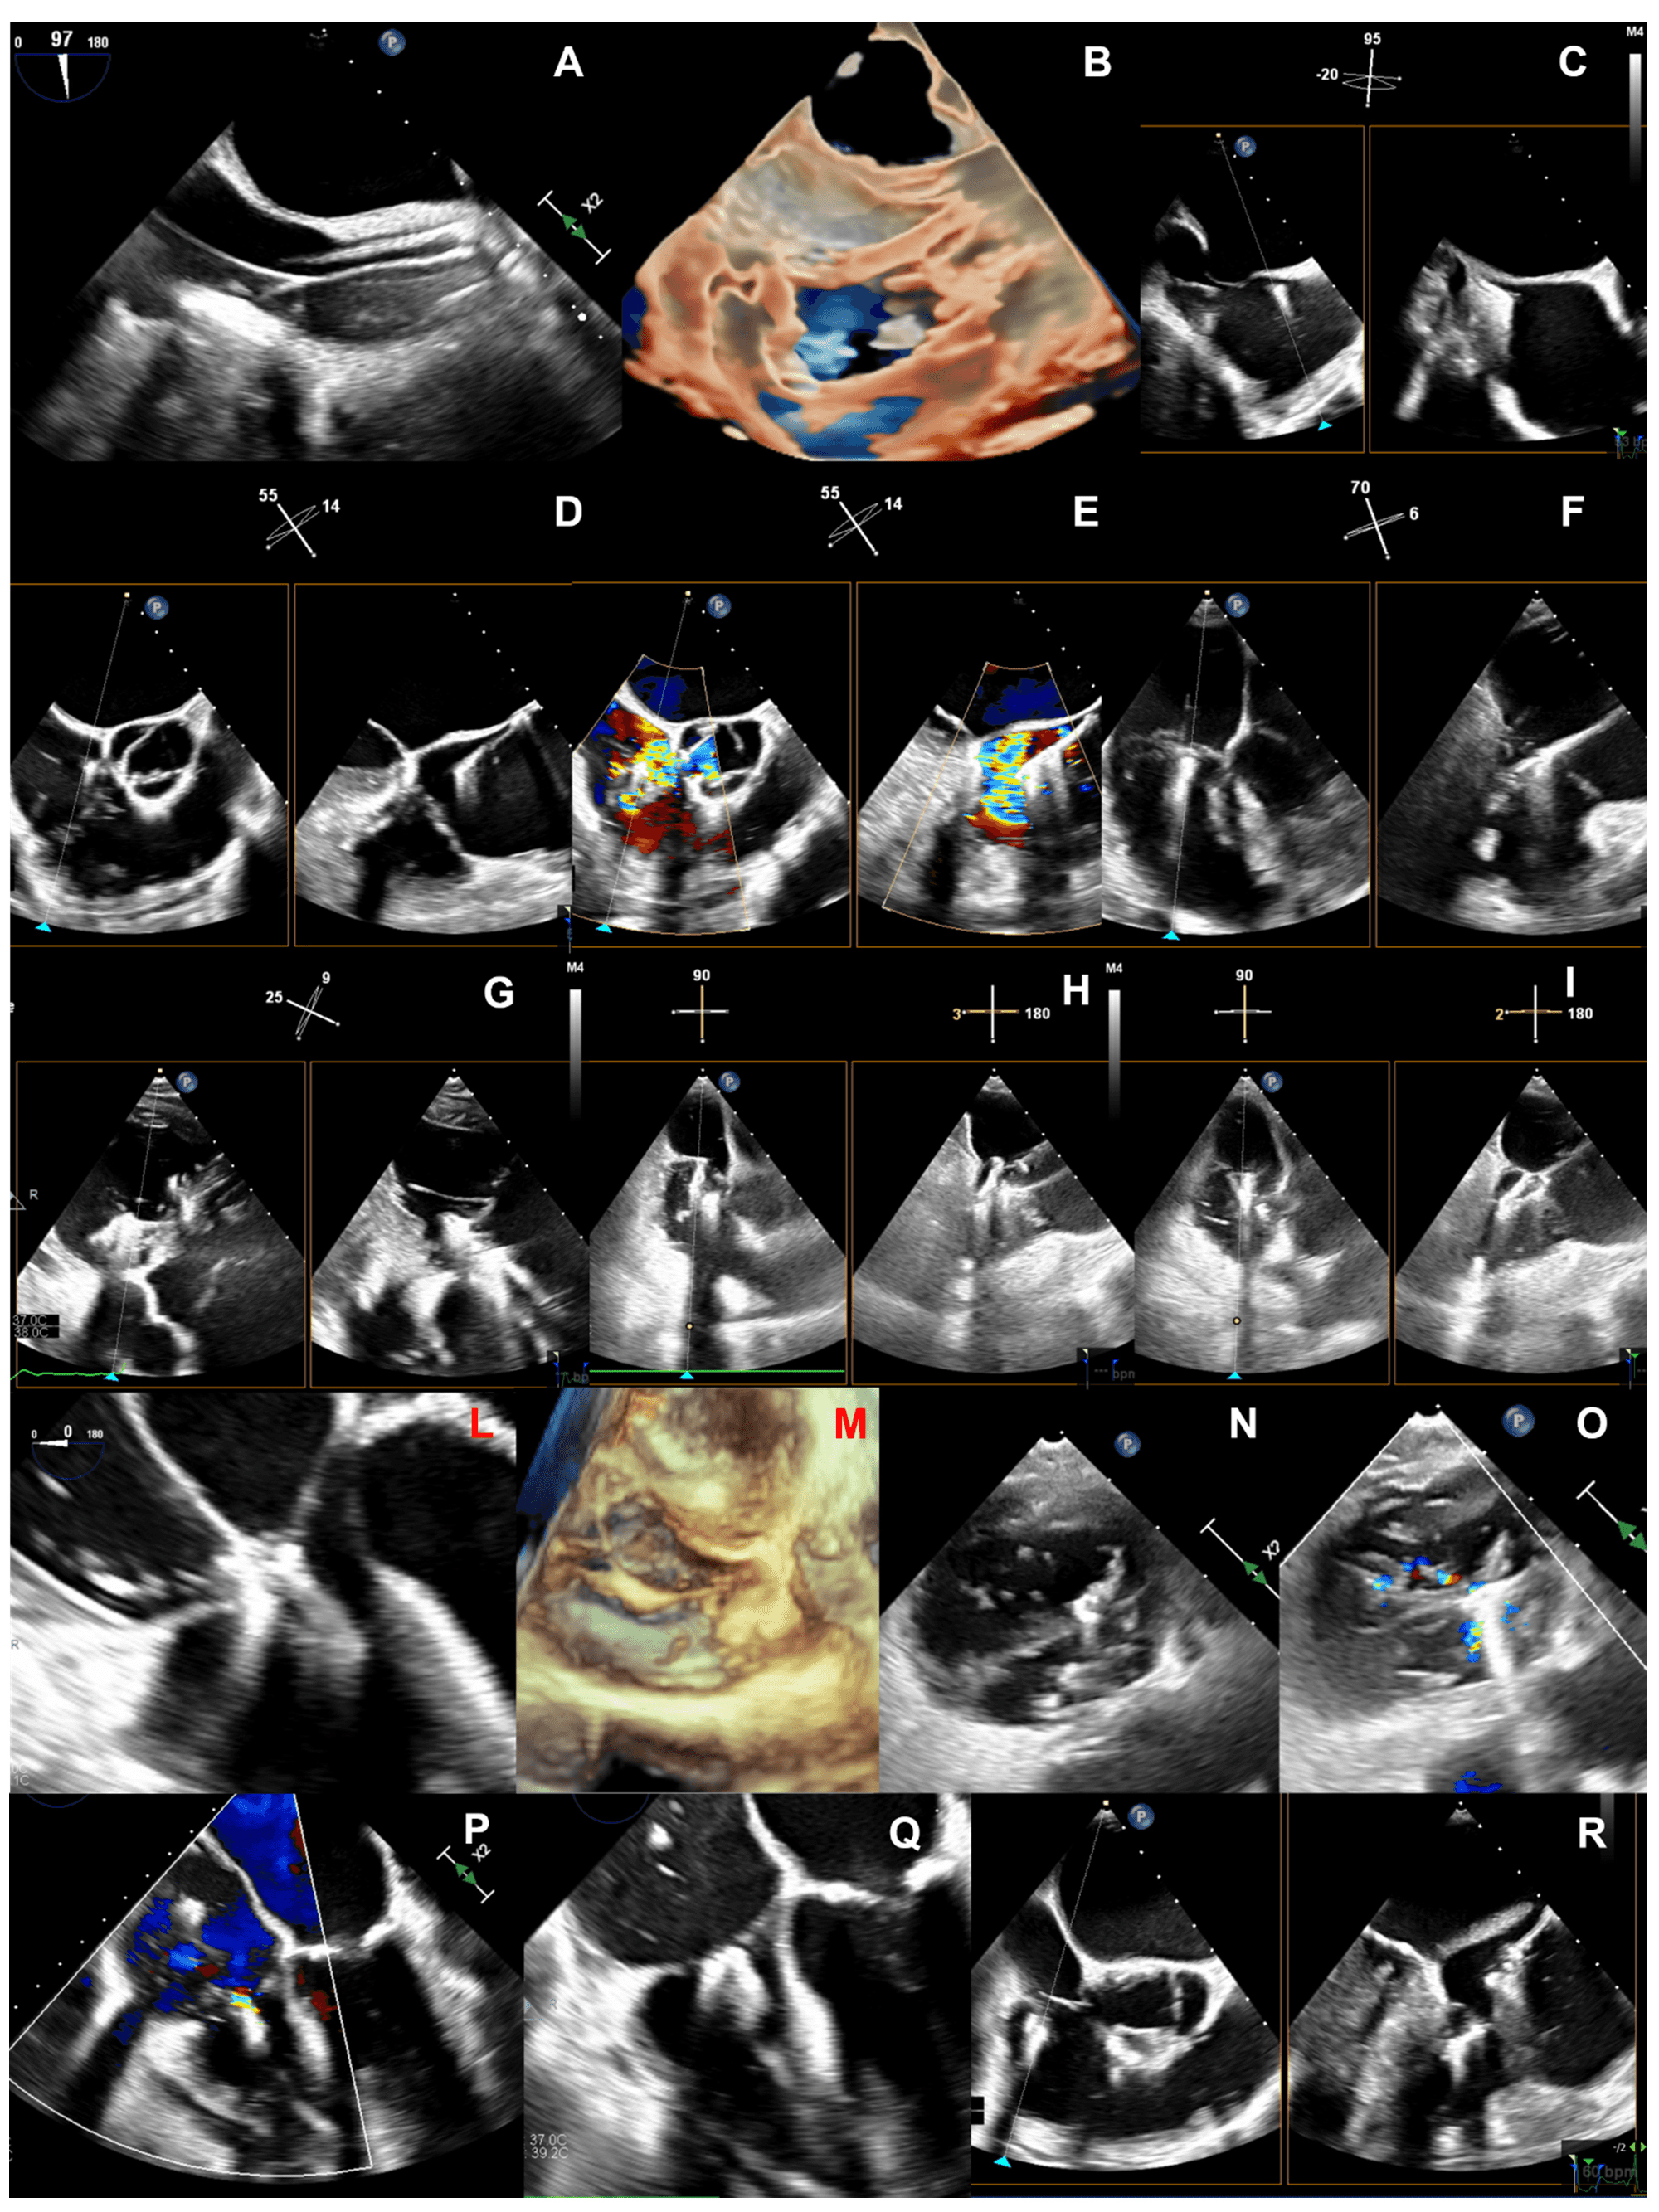

A comprehensive TEE examination of the TV should include multiple windows from several depths and angles and the recurring use of biplane (or crossplane) modality [2, 38, 39].

The multilevel assessment of the TV classically begins at a mid-esophageal (ME)

depth with two views (Table 2): ME 4-chamber view (at about 0

| Abbreviations: AL, anterior leaflet; DE, deep-esophageal; DT, deep-transgastric; ME, mid-esophageal; PL, posterior leaflet; PV, pulmonary valve; RV, right ventricle; SL, septal leaflet; TG, transgastric; TV, tricuspid valve. |

At deep-esophageal (DE) level the probe becomes closer to the RA and the TV without the interposition of the left atrium. Due to this proximity, DE views are optimal for 3D acquisitions of the TV and for Doppler beam alignment with regurgitant jets. Like at ME level, main DE views are the 4-chamber and the RV inflow-outflow.

At trans-gastric (TG) level unlimited views of the TV may be imaged, with a meticulous manipulation of the probe (usually right and anterior flexion) and use of different angles and biplane mode. The SAX view of the TV is crucial to assess the valve anatomy (number and morphology of leaflets, presence of clefts/fold indentations), to identify the regurgitant orifice and to measure the coaptation gap size. This view is required for assessment of the TV anatomy according to the above-mentioned classification of Hahn et al. [11]. If a CIED-lead crosses the TV, this view allows to localize where the lead crosses the valve and to assess the presence and entity of a potential CIED-related interference with leaflet coaptation.

Finally, deep-transgastric (DT) views of the TV may be useful mainly for colour flow evaluation and optimal Doppler beam alignment. In case of intense shadowing of the TV at ME and DE levels due to the interposition of atrial septum, aortic and mitral valves, this window permits to solve this issue.

Given the limitations and challenges of 2D echocardiography for TV assessment, 3D imaging is nowadays recommended to provide an exhaustive evaluation of leaflets, annulus and subvalvular apparatus. 3D datasets may be acquired from any good-quality TTE or TEE view [28]. The TTE apical (RV-focused or foreshortened) and parasternal RV inflow views are generally the best approaches to achieve an optimal TTE 3D acquisition of TV, while the TEE DE view permits to reduce at minimum the distance between the TEE probe and the right heart and to acquire fulfilling 3D datasets [40, 41]. A good 3D acquisition always derives from a 2D view which has been adequately optimized in terms of gain, with a high tissue-blood contrast and low speckle noise. To achieve the best spatial resolution of 3D datasets, it is pivotal to maintain the whole TV within a small acquisition volume, while optimizing the acquisition volume size and shape, and the gain and temporal resolution settings. To comprehensively evaluate the anatomy of the TV, the valve is generally visualized “en face” from both the ventricular and the atrial perspectives. The atrial (or surgical) view is particularly useful when analysing a primary TR, as it allows a detailed assessment of the motion of the leaflets; the ventricular perspective provides information regarding the involvement of commissures or fold indentations into TR mechanism, the presence of a leaflet/chordal impingement due to a CIED or the entity/location of the regurgitant orifice. A multibeat acquisition is generally preferred, as it provides the highest resolution and frame rate. However, in presence of arrhythmias or marked respiratory variations, multibeat acquisitions are prone to stitching artifacts. Real-time or live 3D is particularly useful for the guidance of transcatheter procedures as it is less susceptible to motion artifacts and the use of real-time multiplanar reconstruction (MPR) allows rapid orientation within the 3D dataset. The above-mentioned anatomic landmarks (aortic valve, septum, coronary sinus) for leaflet identification need to be encompassed within the 3D dataset, in order to allow a correct interpretation of the 3D TV acquisition [41].

There is not a general agreement regarding the proper orientation of the en-face view of the 3D TV acquisition. Lang et al. [42] proposed to orient the TV with the septal leaflet at 6 o’clock regardless of the atrial or ventricular perspective. More recently, for interventional purposes, Muraru et al. [40] proposed an atrial perspective with the septal leaflet between 6 and 10 o’clock, whereas Agricola et al. [43] oriented the atrial view with superior vena cava (SVC) at 11 o’clock and inferior vena cava (IVC) at 7 o’clock.